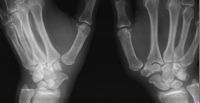

| Preop basal joint stress

views showing subluxation and subsidence: |